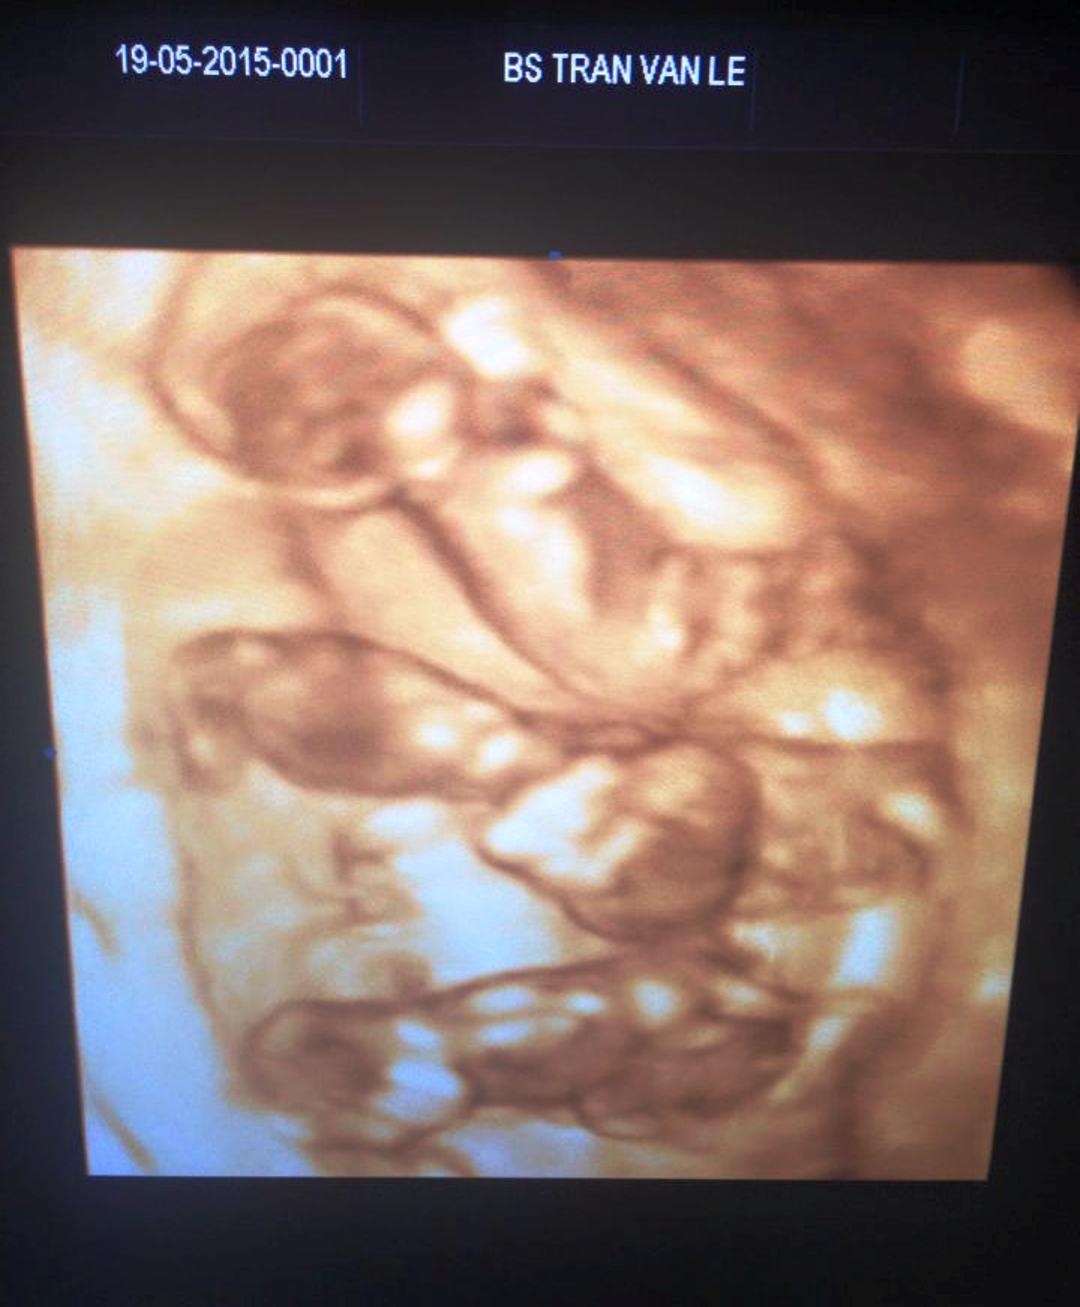

| Hình ảnh bào thai của chị Xuân được đưa lên facebook. Ảnh: FB Lê Huyền Lê. |

Đó là chị Hoàng Thị Xuân (26 tuổi, trú xã Hưng Trạch, huyện Bố Trạch). Khi bác sĩ Lễ rà đi rà lại đầu dò convex trên bụng chị Xuân, hình ảnh của 4 túi thai hiện ra rõ nét trên máy siêu âm.